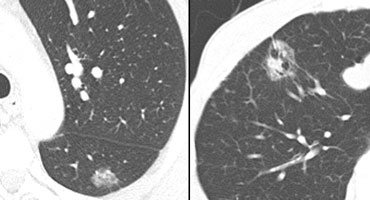

Partly solid nodule containing ground-glass component most likely to be malignant Partly solid nodule containing ground-glass component most likely to be malignant

Solid and Ground-glass components

Another result from screening studies is that nodules containing a ground-glass component are more likely to be malignant (5).

• Partly solid lesions with ground-glass components had a malignancy rate of 63%.

• Nonsolid - only ground-glass lesions had a malignancy rate of 18%.

• Only solid lesions had a malignancy rate of only 7%.

LEFT: 1 in 5 malignantRIGHT: 2 in 3 malignant LEFT: 1 in 5 malignantRIGHT: 2 in 3 malignant

On the far left a lesion that only has a ground-glass appearance and next to it a lesion that has both ground-glass and solid components.

The likelihood of malignancy is 1:5 for the lesion on the far left and 2:3 for the lesion with both ground-glass and solid components.